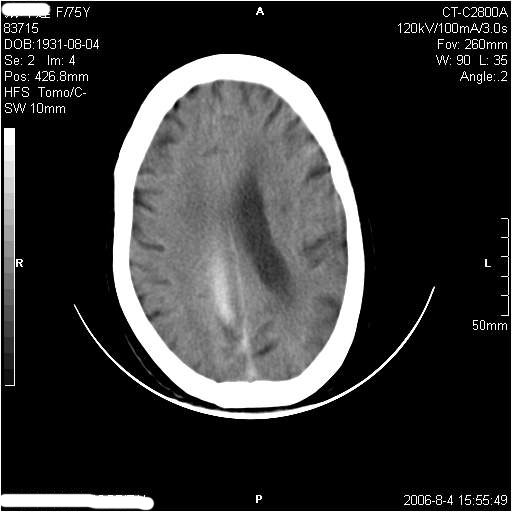

左侧偏瘫3天.

1纵裂硬膜下血肿,2双基底节脑软化灶.

1、纵裂硬膜下血肿,2、右侧室前角旁梗塞;3、双基底节脑软化灶.

镰旁慢性硬膜下出血?双侧多发腔梗。

有摔倒外伤史,另看右侧灰白质界限.

双侧基底节区多发性腔梗.引起临床症状的主要原因是右侧侧脑室旁的梗塞病灶.

应该是右侧大脑镰旁的血肿,右侧基底节区脑梗塞。

1、该患者从脑实质表现情况看应该年龄较大了,双侧基底节区多发斑片状低密度灶,侧脑室旁白质密度减低,各脑室腔扩大,脑沟裂增宽加深,以上改变符合:皮层下动脉硬化性脑病。

2、上纵裂右侧梭形条状高密度影阴,边缘模糊,周围水肿带环绕,右侧脑室受压变形,有摔倒外伤史,多考虑:纵裂硬膜下血肿。

支持纵裂硬膜下血肿,应该是慢性,或是再出血.